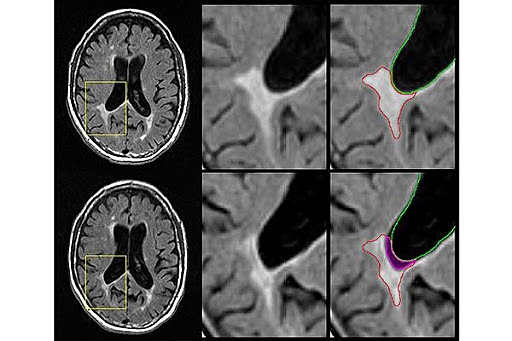

• Equipos Tecnologicos

Equipos Tecnologicos

En la evolución de la ciencia se han creado equipos los cuales pueden evidenciar infinidad de lesiones y/o enfermedades que se tienen sin necesidad de realizar cirugías, se conocen como técnicas no invasivas.

Algunas tecnicas:

Resonancia magnética funcional

Estimulación magnética transcraneal

Electroencefalografía